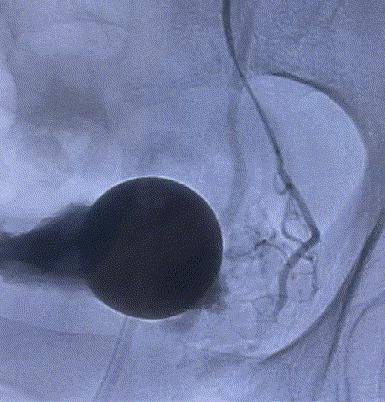

随後,李旭丹主任攜手胡志華主任爲患者實施介入治療,采用改良Seldinger法穿刺股動脈,在DSA引導下經動脈自然腔道,将微導管分别送達雙側髂内動脈進行造影,觀察雙側前列腺動脈分布情況,将微導管超選擇至雙側前列腺動脈,準确置入PVA栓塞材料,成功阻斷前列腺的營養供給,順利完成了治療。

△術前,可見前列腺供血豐富。